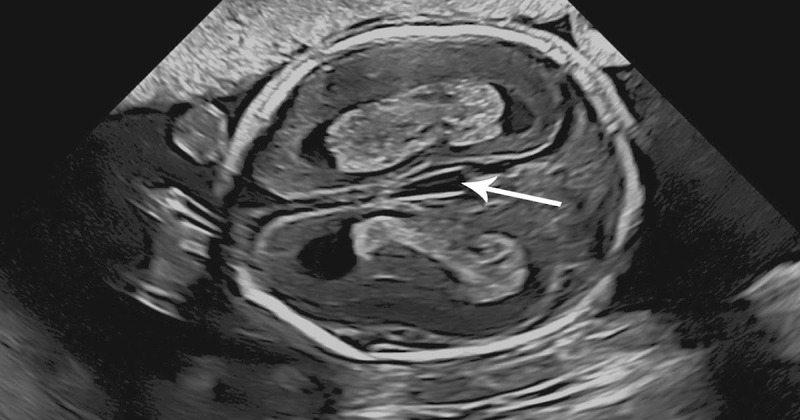

Tính dựa trên siêu âm

Siêu âm giúp xác định tuổi thai một cách chính xác hơn, đặc biệt là trong giai đoạn đầu của thai kỳ (3 tháng đầu). Siêu âm có thể đo kích thước của phôi thai và tính toán tuổi thai từ đó.

- Bước 1: Siêu âm lần đầu (thường trong 6-8 tuần sau khi bạn có thai).

- Bước 2: Bác sĩ sẽ đo kích thước của phôi thai và dựa vào đó xác định tuổi thai, từ đó tính ra ngày dự sinh.

Phương pháp này đặc biệt chính xác khi bạn không nhớ rõ ngày kỳ kinh cuối cùng hoặc khi chu kỳ của bạn không đều.